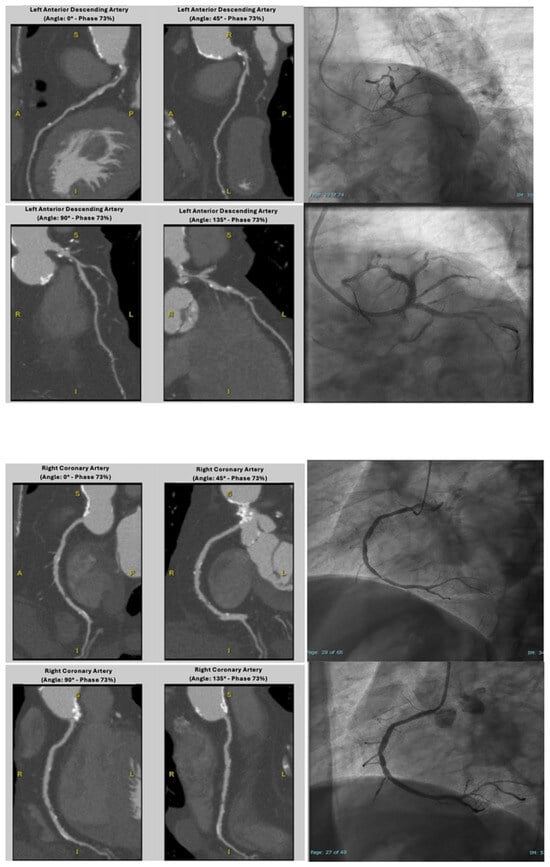

Diagnostic Accuracy of Coronary CT Angiography in Ruling Out Significant Coronary Artery Disease in Candidates for Transcatheter Aortic Valve Replacement

by Chiara Gallo, Alfonso Campanile, Carmine Izzo, Sonia Paoletta, Valentina Russo, Pierpaolo Chivasso, Francesco Vigorito, Marco Di Maio, Michele Ciccarelli, Amelia Ravera, Tiziana Attisano, Giuliano Maraziti, Davide Di Gennaro, Enrico Coscioni, Carmine Vecchione and Oliviero Caleo

J. Cardiovasc. Dev. Dis. 2025, 12(10), 395; https://doi.org/10.3390/jcdd12100395 - 6 Oct 2025

Obstructive coronary artery disease (CAD) is common in patients undergoing transcatheter aortic valve implantation (TAVI). While invasive coronary angiography (ICA) is the gold standard for coronary evaluation, coronary computed tomography angiography (cCTA) is gaining interest for its potential to exclude obstructive CAD during [...] Read more.

Obstructive coronary artery disease (CAD) is common in patients undergoing transcatheter aortic valve implantation (TAVI). While invasive coronary angiography (ICA) is the gold standard for coronary evaluation, coronary computed tomography angiography (cCTA) is gaining interest for its potential to exclude obstructive CAD during pre-procedural imaging. This study aimed to assess the diagnostic accuracy of cCTA in ruling out significant CAD in TAVI candidates. We retrospectively analyzed 95 TAVI candidates (mean age 77.7 ± 8.5 years) who underwent both cCTA and ICA. Diagnostic performance of cCTA—sensitivity, specificity, positive predictive value (PPV), negative predictive value (NPV), and accuracy—was assessed using ICA as the reference, in both patient- and vessel-based models. Obstructive CAD was defined as ≥50% luminal stenosis or occlusion of a stent/bypass graft. ICA detected obstructive CAD in 27 patients (28.4%). Excluding non-evaluable cases, cCTA showed a negative predictive value (NPV) of 97% (patient-level) and 95% (vessel-level), with a diagnostic accuracy of 85% and 87%, respectively. Including all patients, regardless of scan quality, the NPV remained high (97%), although overall accuracy dropped to 67% (patient-level) and 66% (vessel-level). cCTA demonstrated high accuracy in excluding significant CAD, with a stable NPV of 95–97%. The relatively high rate of non-diagnostic scans and the single-center, retrospective design suggest that its role should be considered complementary to ICA, potentially reducing—but not replacing—the need for ICA in selected TAVI candidates. Full article

Show Figures

Figure 1